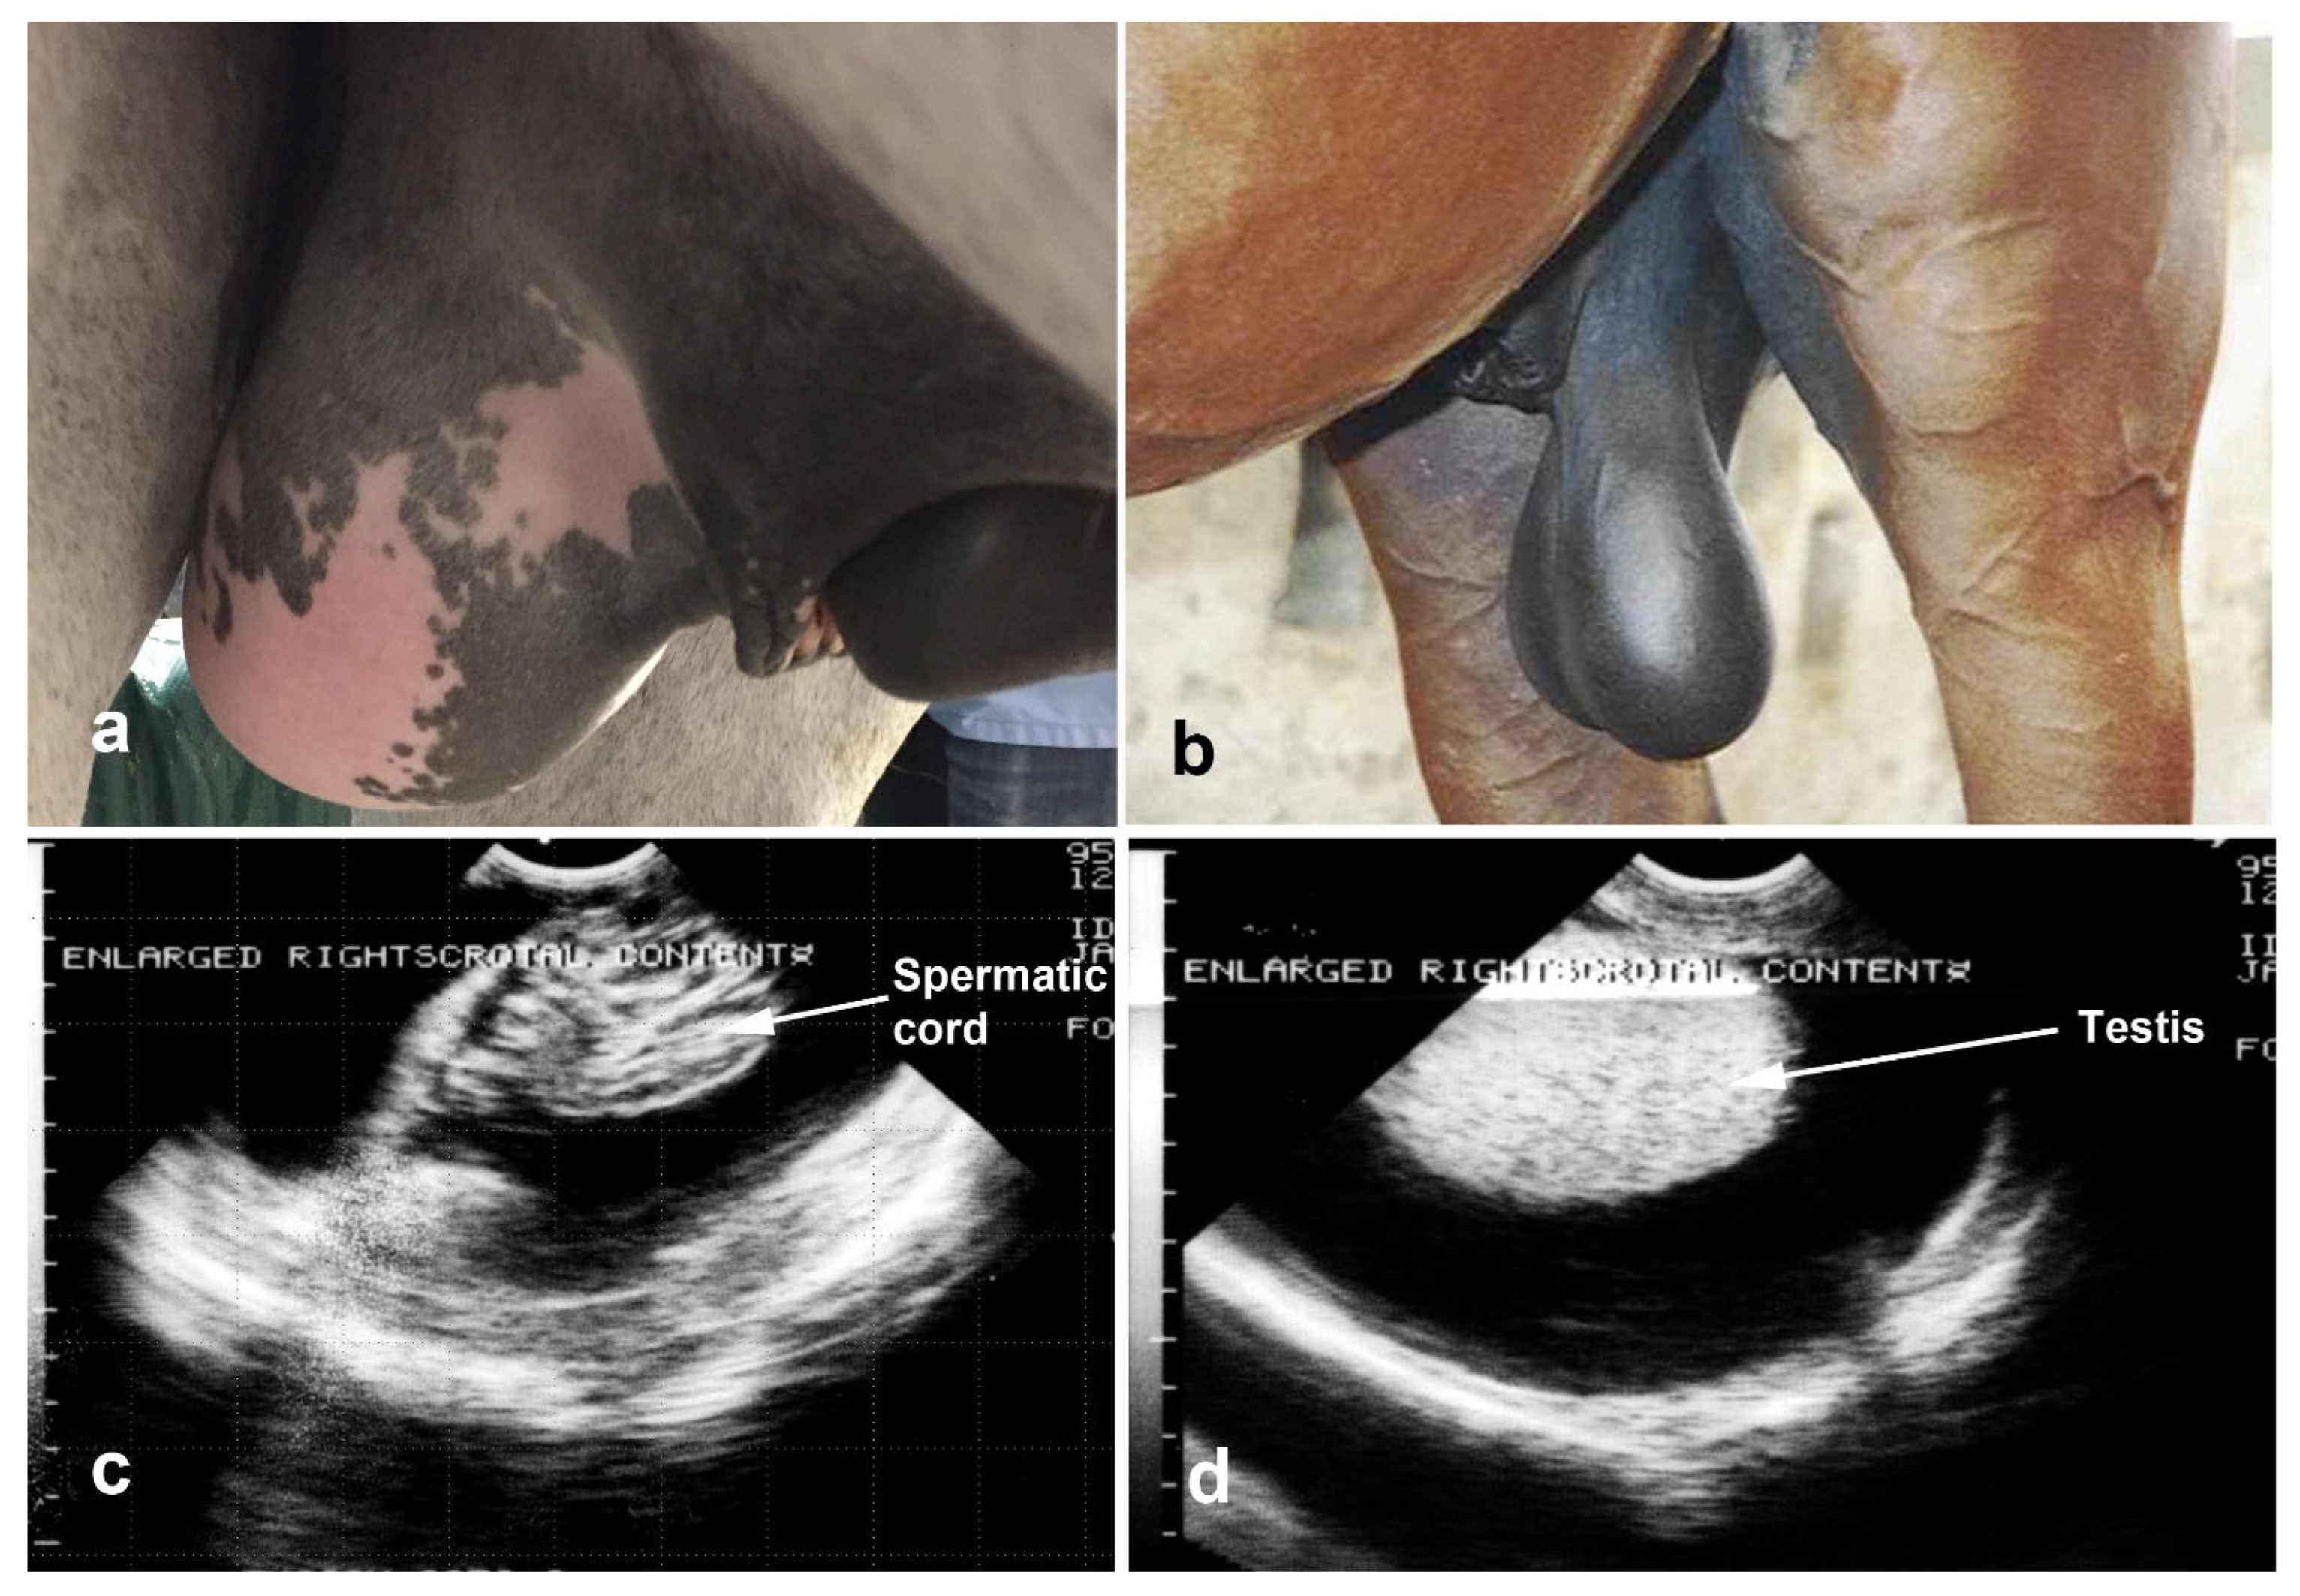

4.2. Acquired Scrotal/Inguinal Hernia

- François, I.; Lepage, O.M.; Schramme, M.C.; Salciccia, A.; Detilleux, J.; Grulke, S. Clinical Findings, Surgical Techniques, Prognostic Factors for Short-Term Survival and Long-Term Outcome in Horses with Acquired Inguinal Hernias: Ninety-Eight Cases (2005–2020). Vet. Surg. 2024, 53, 468–476. [Google Scholar] [CrossRef] [PubMed]

- Mezerová, J.; Žert, Z.; Kabeš, R.; Jahn, P. Hernia Inguinalis Incarcerata in Horses: 43 Cases. Pferdeheilkunde 2003, 19, 263–268. [Google Scholar] [CrossRef]